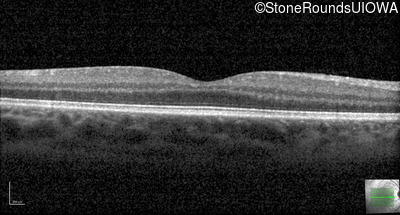

Optical Coherence Tomography - Right - 20/25

Exemplar / OCT Stack